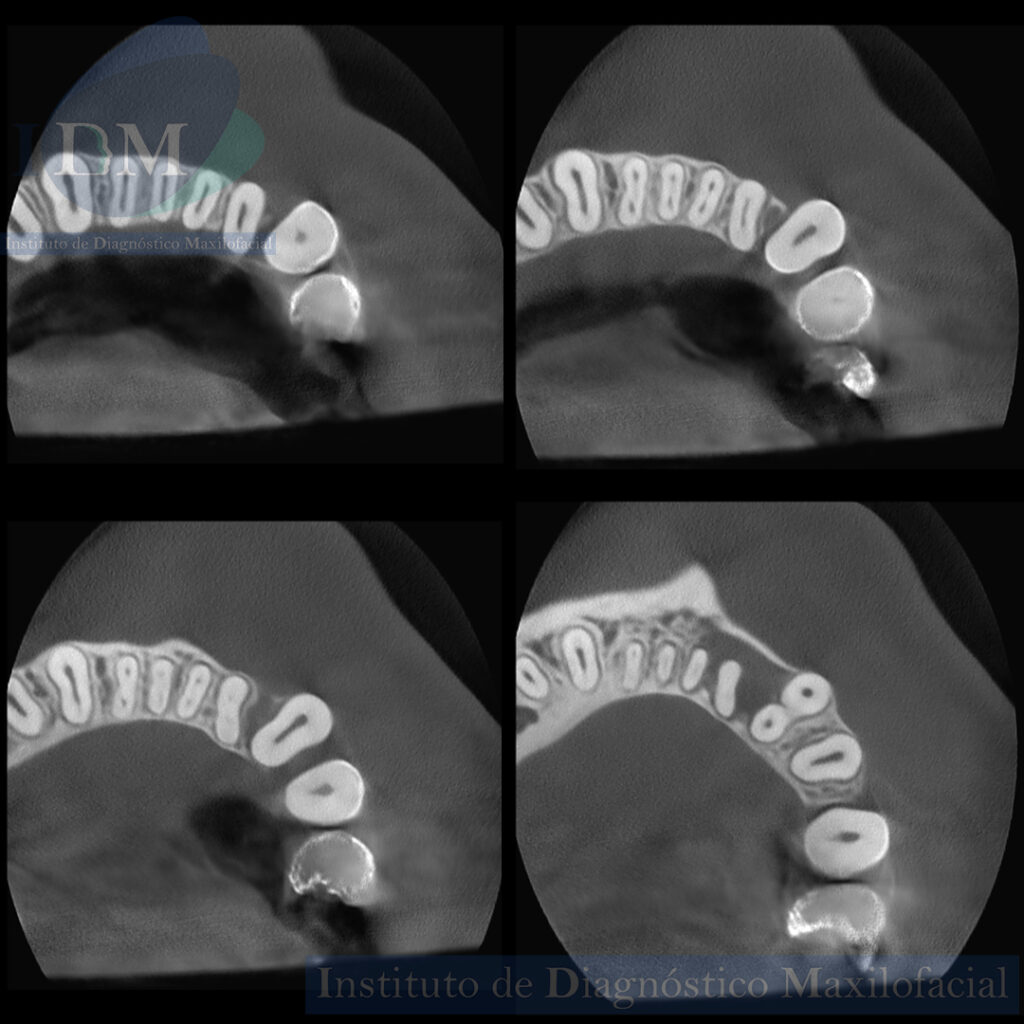

A la evaluación de la tomografía volumétrica (CBCT) en los cortes axiales (Figura 2) y transaxiales (Figura 3), se aprecia proceso osteolítico periapical en pieza 32 que ocasiona el borramiento parcial de la lámina dura de piezas 33 y 31, a la vez se evidencia presencia de dos conductos a nivel de tercio cervical y medio que convergen a nivel apical en piezas 32, 31, 41, 42.

CORTES AXIALES